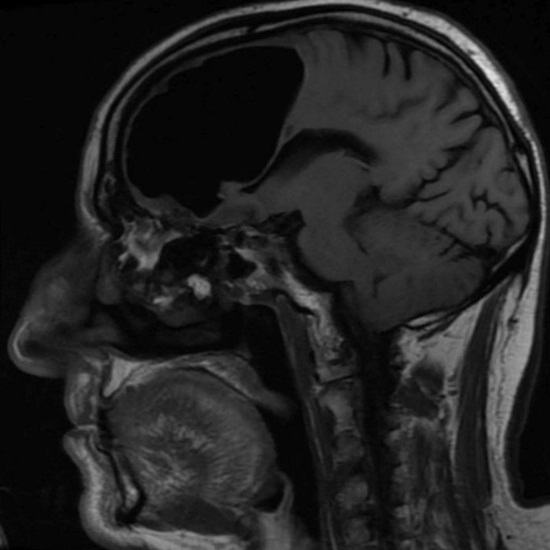

Lékaři ze Severního Irska byli při vyšetřování ohromeni v poslední době 84-letý pacient, který k nim přišel s malátností. Po provedení magnetické rezonance na hlavě muže, lékaři nečekaně zjistil, že mu chybí část pravého frontálu laloky mozku. Místo toho v lebce důchodce byl vzduch kapsa. Pak lékaři určili, že skutečný fragment mozku pacient nikam nezmizel, ale byl smíchán ve směru této abnormální dutina.

Personál nemocnice navrhl, že pacient se chová obtížně operace odstranění vzduchové kapsy, ale muž odmítl z chirurgie. Podle důchodce, pro jeho věk, obvykle se cítí velmi dobře a ne má v úmyslu ohrozit svůj život tím, že leží pod skalpelem. Do naštěstí brzy Irův blahobyt zmizel a v současnosti ve chvíli, kdy nepociťuje žádné nepohodlí spojené jejich neobvyklý zdravotní stav.